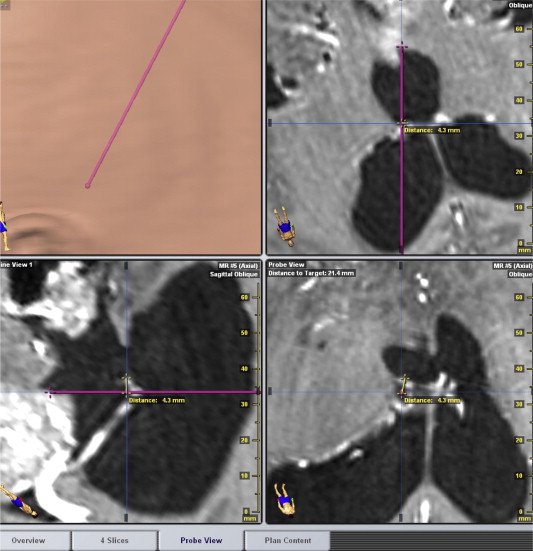

Measurement of the virtual displacement for endoscopic tumor biopsy in ...

Figure 4.

Measurement of the virtual displacement for endoscopic tumor biopsy in neuronavigation software (probe view): Case 3, displacement = 4.3 mm.